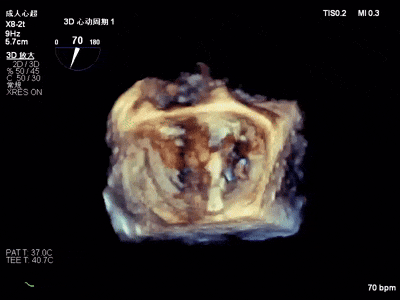

术中超声要点

术前术后对比图

术前

术后

术后,出院检查报告显示夹子位置固定,二尖瓣、三尖瓣及主动脉轻微反流,左房增大,左室内径正常上限,EF值正常下限(WMSI 1分)。